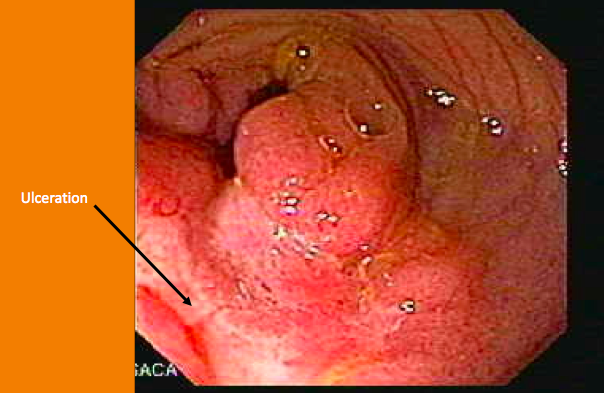

Ulcereation in the small bowel in pt. 2

Not really ulcerated, just lots of inflammation

B: No vasculature (non-specific- ischemia, infection, etc) or ULCERS (its still UC)